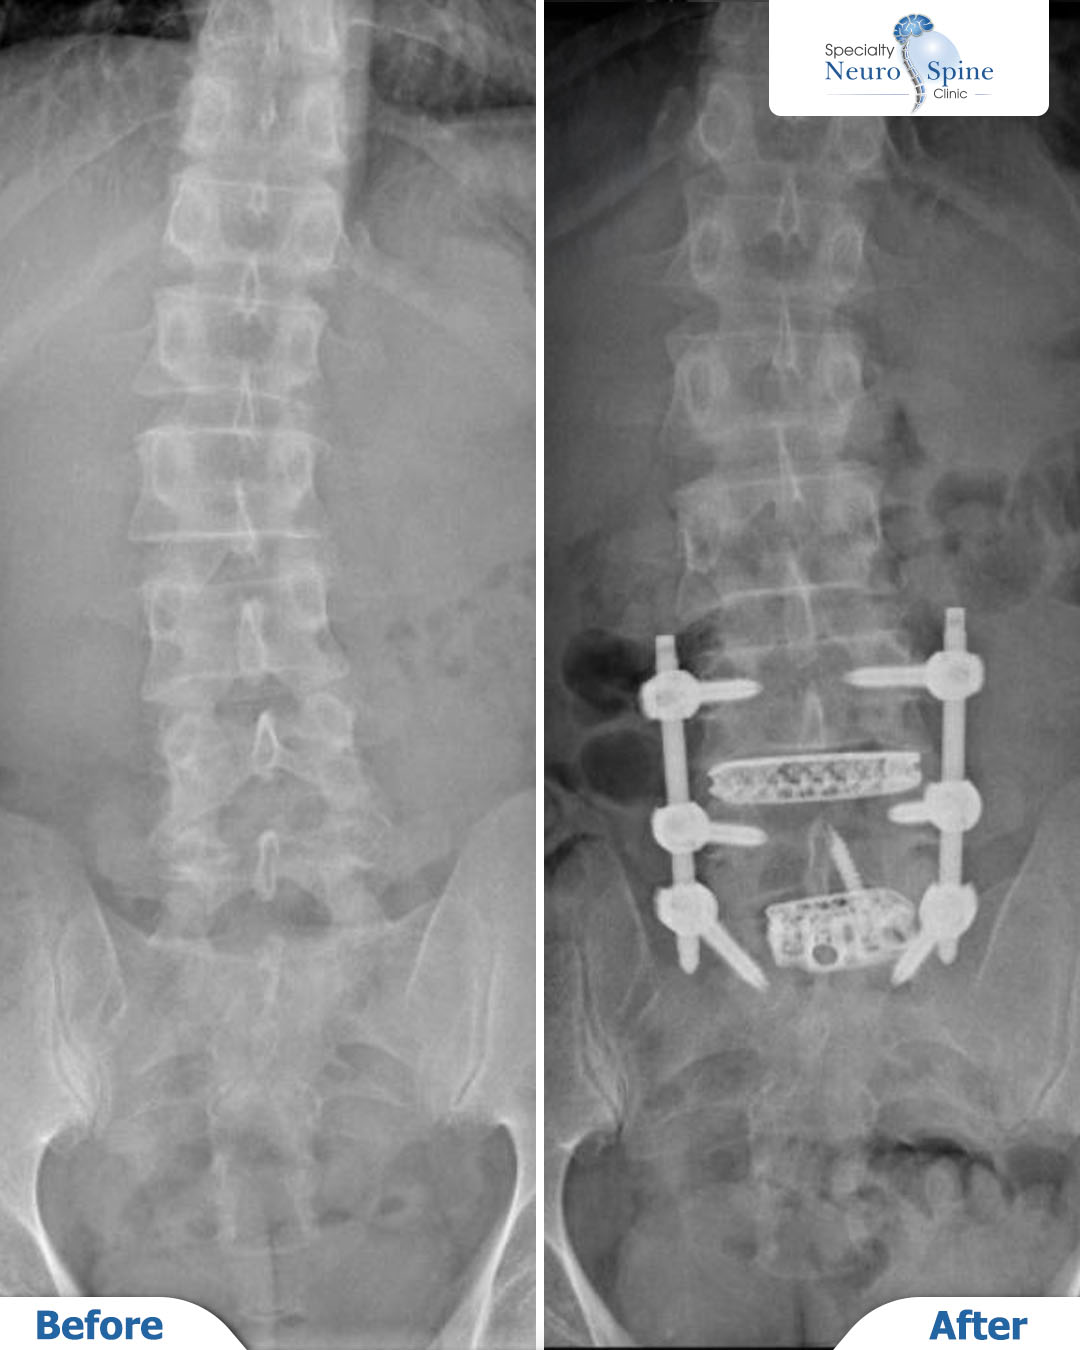

The X-ray images of our patient, Muzmli (44 years old, from India), illustrate the transformation following an OLIF (Oblique Lumbar Interbody Fusion) procedure at the L4-L5 and L5-S1 levels, alongside neural decompression.

The images clearly demonstrate the restoration of spinal alignment and robust fixation achieved with interbody cages and screws. This has effectively eliminated the compression that was causing his chronic back pain and sciatica.